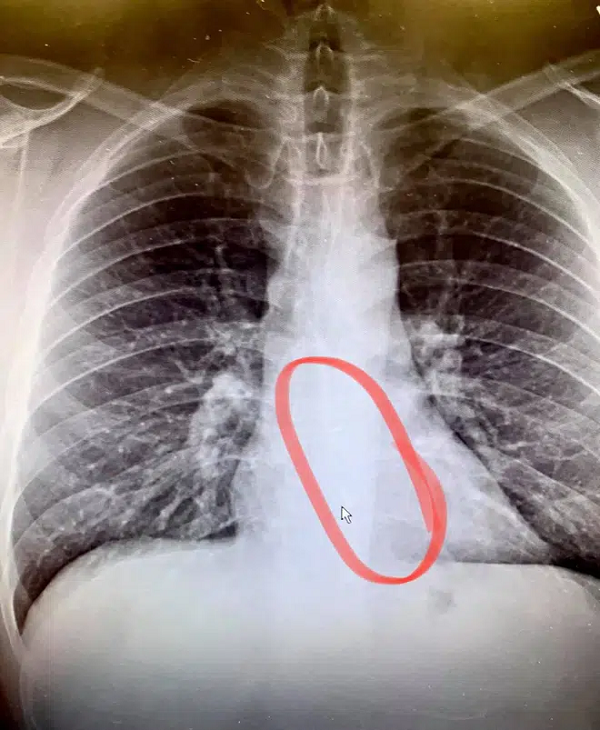

Tại bệnh viện, ảnh chụp X-quang cho thấy một chiếc AirPods đang nằm trong thực quản của Gauthier. Bác sĩ phải mổ nội soi khẩn cấp để lấy dị vật khỏi cơ thể ông